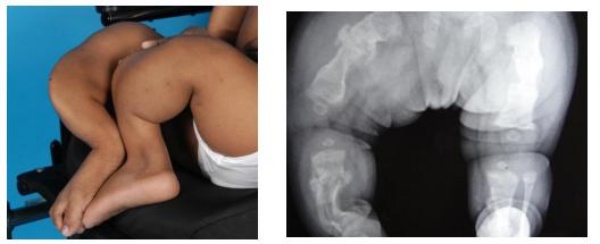

Bệnh tạo xương bất toàn (Osteogenesis imperfecta: OI) là bệnh lý đột biến gen dẫn đến rối loạn chuyển hóa mô liên kết biểu hiện là xương dễ gãy đặc biệt là xương dài. Các biểu hiện lâm sàng khác bao gồm: giác mạc ngả màu xanh (blue sclerae), thấp lùn, thiểu sản răng, nghe kém…Các biểu hiện khác có thể gặp nhưng ít ngiêm trọng hơn như: lỏng khớp toàn thân, thoát vị rốn, dễ bầm tím, ra mồ hôi quá mức…

❖ Xương dài: Hay gặp nhất là gãy xương do chấn thương nhẹ, thường gặp nhất là xương chi dưới trong đó xương đùi nhiều hơn xương chày. Có thể gãy xương không do chấn thương. Không có kiểu hình gãy nào là đặc hiệu cho OI. Thường xương gãy liền tốt ít khi tạo khớp giả. Ổ can xương thường mỏng. Gãy đi gãy lại dẫn đến biến dạng trục chi, cứng khớp, hạn chế hoặc mất vận động. Trẻ không lớn được do các vi chấn thương ở sụn tiếp. Tuổi thường hay bị gãy xương nhất là sau khi dậy thì và có thể kéo dài đến khi mãn kinh ở các trẻ gái. Biến dạng cong xương dài là do lặp đi lặp lại các đường gãy ngang và sự co kéo các cơ qua ổ gãy thân xương. Thường thì xương đùi sẽ cong ra phía trước ngoài, xương chày cong phía trước trong, xương cánh tay cong ra trước ngoài, xương cẳng tay hạn chế sấp và gập góc đầu gần. Khớp khuỷu hạn chế động tác gấp.

❖ Xương dẹt: Kiểu hình mặt của bệnh tạo xương bất toàn được mô tả như người đội mũ bảo hiểm (helmet head) với xương trán thì nhô ra trước, tai thì xuống dưới và ra ngoài… Khung chậu thì nhô ra trước.

❖ Dáng đi: Người lùn thấp do hậu quả của (1) biến dạng chi như gập góc tại ổ gãy của các xương dài (2) chấn thương sụn tiếp. Dáng đi trendelenburg nếu có hiện tượng tăng góc cổ thân xương đùi (coxa vaga, 10%)

❖ Xquang: phát hiện gãy xương, biến dạng trục chi, các ổ gãy xương cũ. Các đặc điểm khác có thể phát hiện trên Xquang: vỏ xương mỏng, giảm khoáng hóa, xương sọ giống người đội mũ bảo hiểm… Trong trường hợp điển hình thì kết hợp Xquang và tiền sử gãy xương nhiều lần có thể chẩn đoán OI.